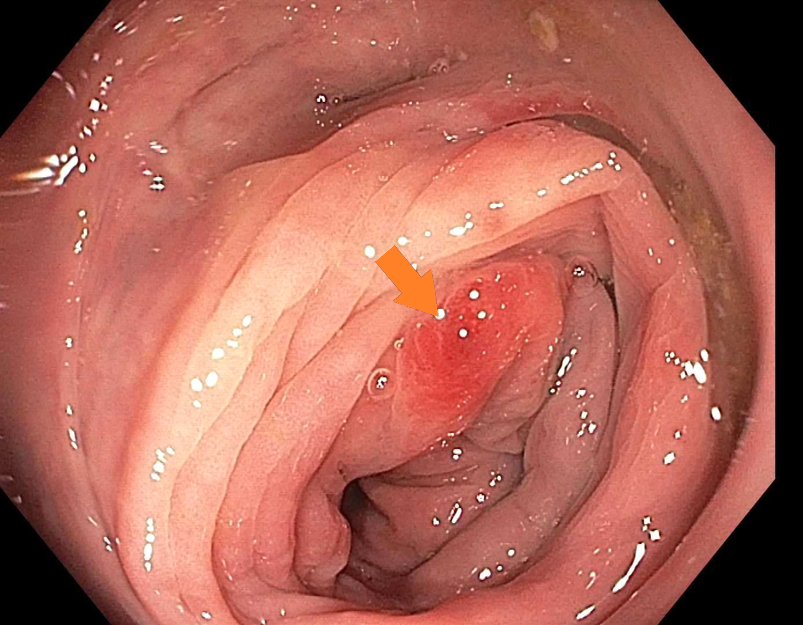

Clinical images

Gross description

- Specimen should be fixed and opened longitudinally for easy sampling of diverticula

- Usually, multiple flask shaped invaginations of colonic wall

- Wall thickening may be present (Surg Endosc 2011;25:2586)

- Narrowing of lumen, shortening of tenia and marked thickening of circular muscle layer may be present (J Clin Gastroenterol 2006;40:S108)

- If it extends deeply, perforation and serosal adhesions may be seen